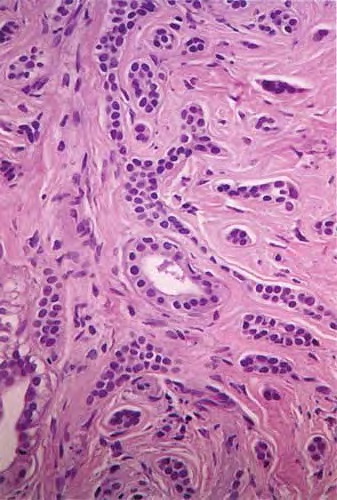

microcystic-adnexal-carcinoma